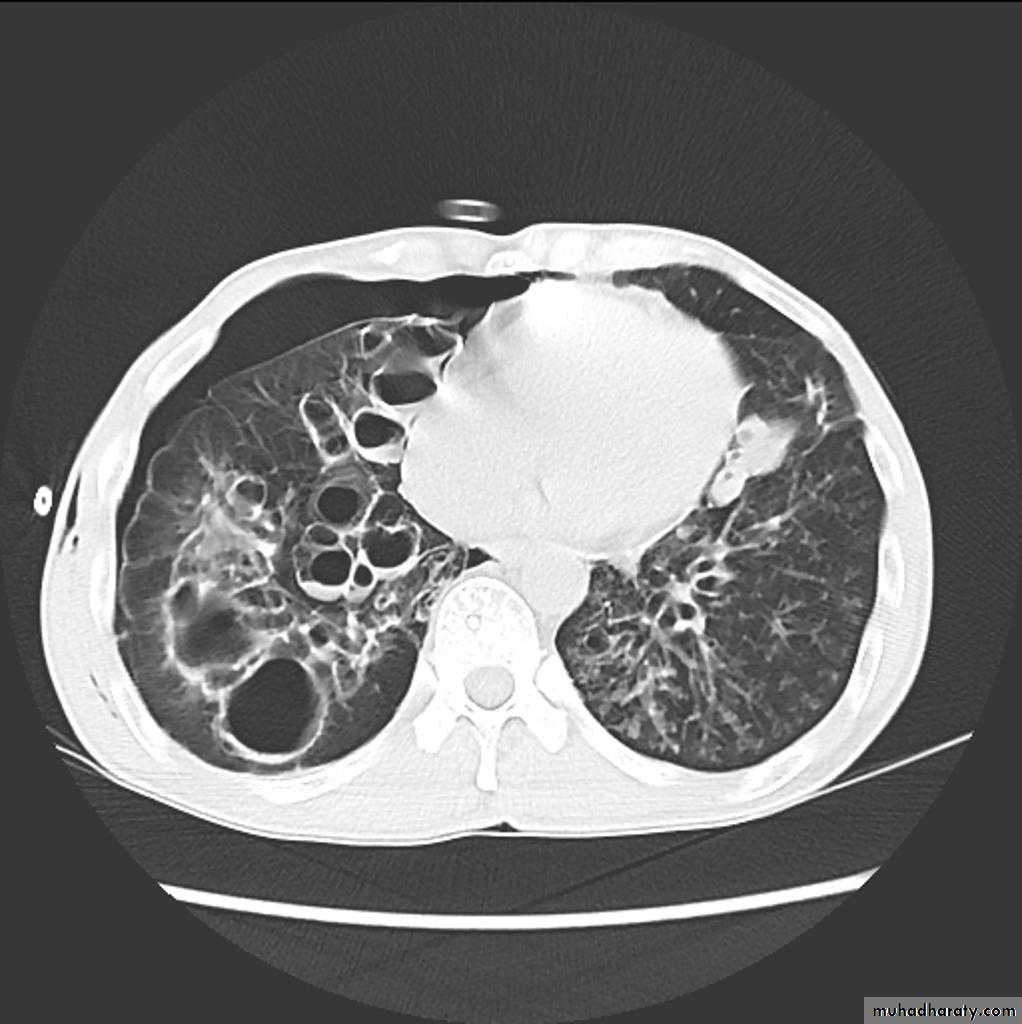

Bronchiactasis

Bronchiectasis refers to abnormal dilatation of the bronchial tree and is seen in a variety of clinical settings. CT is the most accurate modality for diagnosis. It is largely considered irreversibleCauses of bronchiactasias very important to consider

Plain radiograph

Chest x-rays are usually abnormal

1. Tram-track opacities are seen in cylindrical bronchiectasis, and

2. air-fluid levels may be seen in cystic bronchiectasis.

Honey comb shadow

3.Overall there appears to be an increase in bronchovascular markings, and bronchi seen end on may appear as ring shadows .

4.Pulmonary vasculature appears ill-defined, thought to represent peri bronchovascular fibrosis .